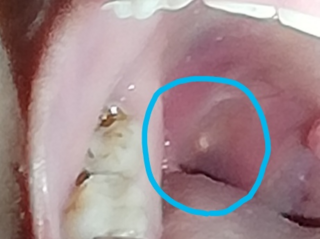

膿栓が見えない どこにあるの 扁桃の裏側 粘膜なので触るのが危ない 膿栓を探して悩み中の人が多数 口臭の教科書